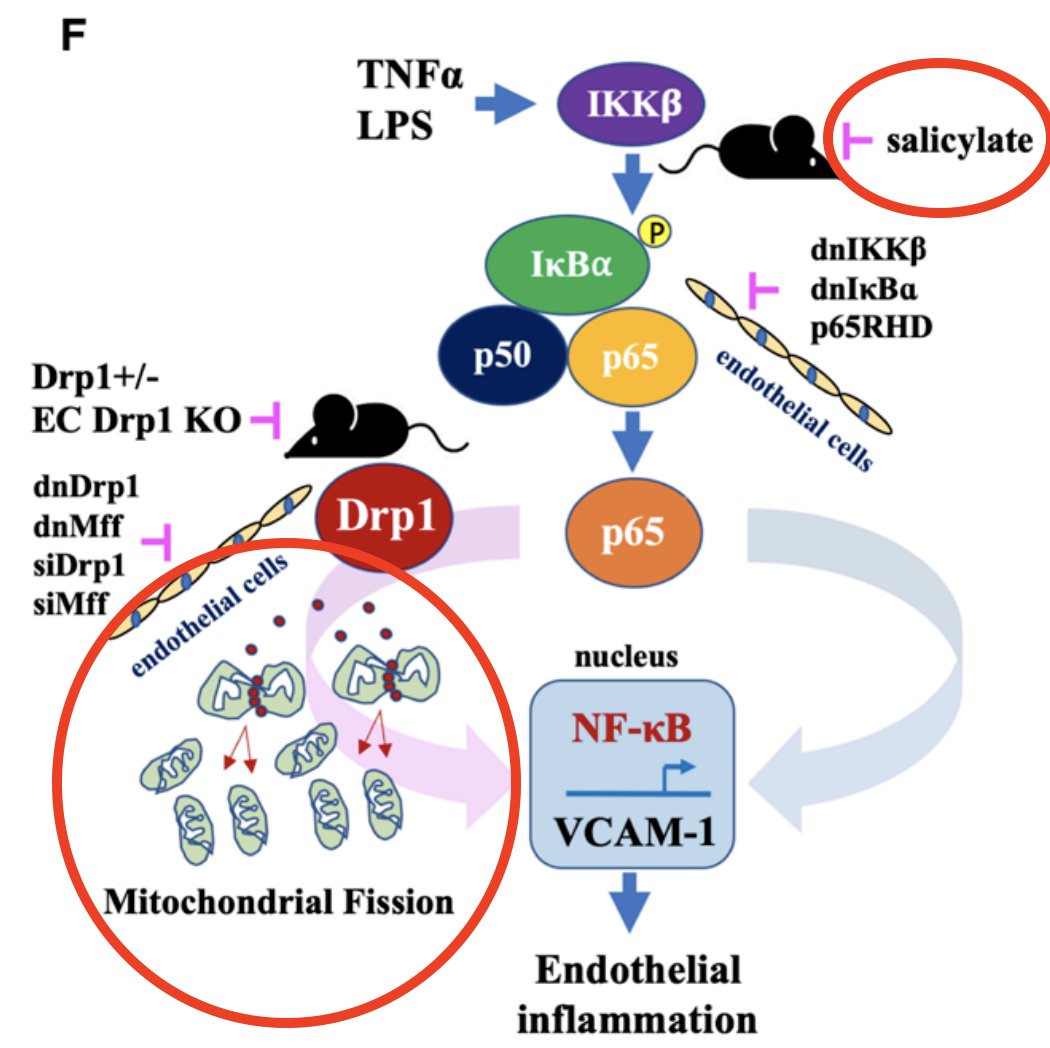

The main aspirin metabolite, salicylic acid, also prevents the structural and functional breakdown of the mitochondria over time.

Aspirin is so therapeutic for such a wide range of ailments because it acts on such basic and fundamental pathways in human health.

‣ Energy production and metabolism

‣ Inflammation, specifically the production of prostaglandins

Aspirin is so therapeutic for such a wide range of ailments because it acts on such basic and fundamental pathways in human health.

‣ Energy production and metabolism

‣ Inflammation, specifically the production of prostaglandins